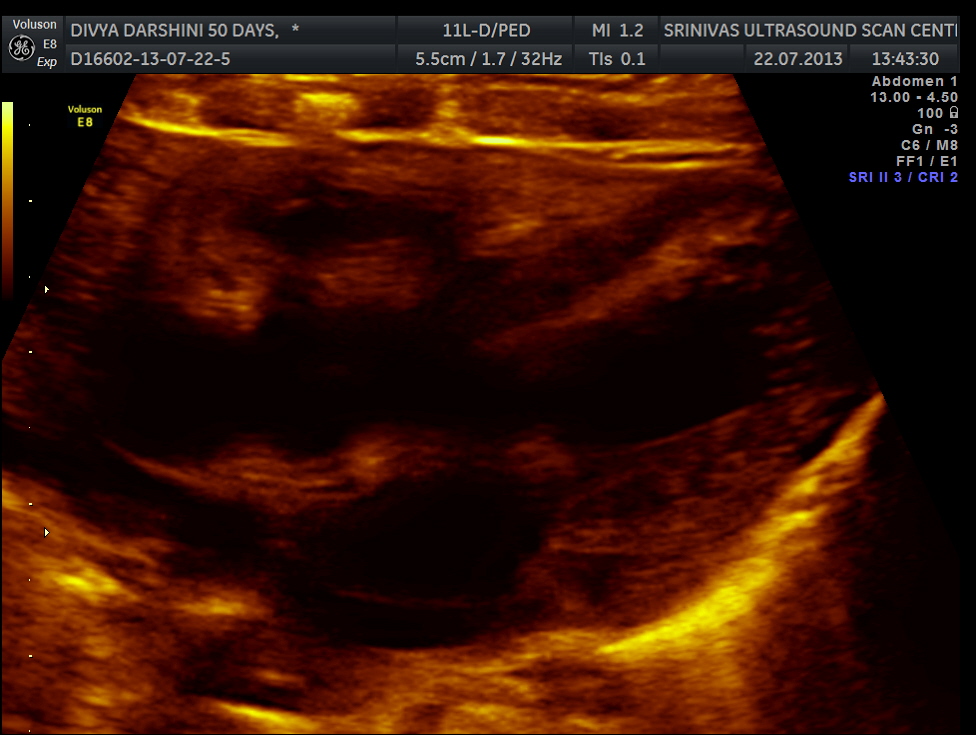

The following two pictures show the hyperechoic kidneys of the child with mild pelvi calyceal dilatation . The kidneys were picked up only with the 11 mhz transducer.